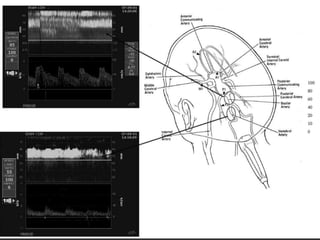

Avaliação primária na identificação dos vasos intracranianos________Profundidade de insonaçãoDireção de fluxo no dopplerVelocidade de fluxosPosição do probeDireção do fluxo no colorImagem dos vasos

Parâmetros diagnóstico_______ Mapeamento em cores do fluxo das artérias intracranianasPadrão da onda do doppler espectral (alargamento espectral, direção de fluxo, aceleração sistólica  e diastólica)Índices ( IP, IR) e velocidades ( Pico sistólico, pico diastólico, VM)Testes funcionaisPadrão de sonorização

Parâmetros diagnóstico_______ Mapeamentoem cores do fluxo das artérias intracranianasPadrão da onda do doppler espectral (alargamento espectral, direção de fluxo, aceleração sistólica e diastólica)Índices ( IP, IR) e velocidades ( Pico sistólico, pico diastólico, VM)Testes funcionaisPadrão de sonorização